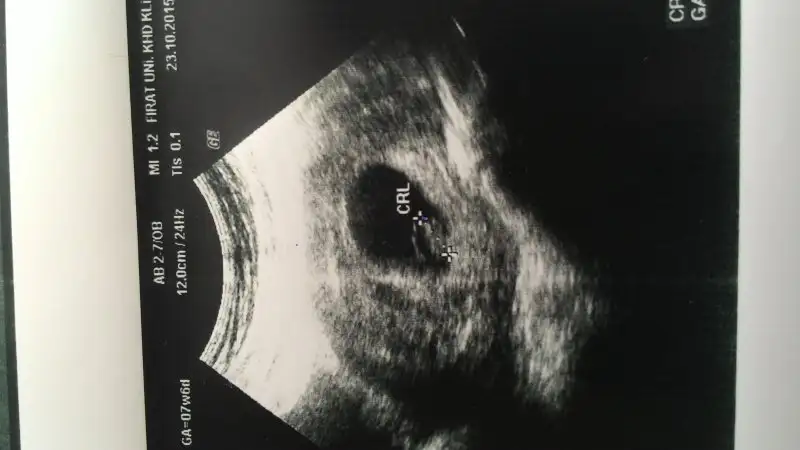

Evet canım sağdaŞimdi kendi usg me tekrar baktım. 6+3 günlük karından. Tekrar bakar mısın canım.

Plasenta sağda gibi gördüm ben

Eki Görüntüle 1715518

Canım nasıl anlıyorsun hangi tarafta olduğunu plasentanın..Evet canım sağda

Canım bu vajinal ultrason ve bebek sağda, teoriye göre erkek, demek ki sen de tutmuyor..

Canım bunda plesenta nerde...Kızlarr bebek değil plasentadan bahsediyorum benn. Benimde ilk kızımda bebek solda, plasenta sağdaydı kız oldu. Bebeğe bakmıcaksınız. Plasentaya bakıcaksınızzz

Benim usg mi sordun sanıp, benimki karından yazmışım pardon canım. Bu fotolar yabancı sitelerden alıntı. Haklısın bunlar vajinal usg. Plasenta sağda görünüyorsa aslında solda doğru canım.Vajinalsa cnm bebek solda olmuş olmuyor mu bu resimde bebek sağda ama vajinal olduğu için bebek solda olmuş olmuyor mu,plasenta zaten soldaymis.

Erkeğe benziyo çünkü solda. Yani aslında sağda karnına tuttuğunda.Canım bunda plesenta nerde...